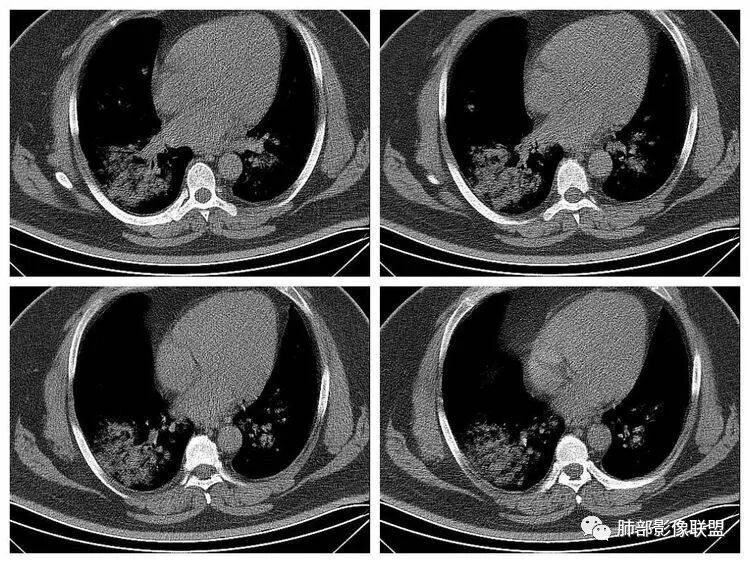

青年男性、急性病史、发热、咳嗽、常规抗炎无效病灶沿支气管血管束分布  GGO+实变边界模糊部分沿胸膜下分布哪几种可能?

南边:1、感染:间质分布——病毒、支原体,支原体一般树芽征明显,累及小气道多,而且临床轻,不太支持2、血管炎,需要相关病史3、肺水肿:心脏不大,无胸水、无中央间质增厚、小叶间隔增厚,不太支持4、PAP,病史影像表现都不支持初学者:可能是病毒,但是好像并不是我们常见的流感病毒实变为主,腺病毒?就是太多灶了一点

重症流感的定义出现以下情况之一者为重症病例1.持续高热>3天,伴有剧烈咳嗽,咳脓痰、血痰,或胸痛2.呼吸频率快,呼吸困难,口唇紫绀;3.神志改変:反应迟钝、嗜睡、躁动、惊厥等4.严重呕吐、腹泻,出现脱水表现;5.合并肺炎6.原有基础疾病明显加重。危重症流感的定义出现以下情况之一者为危重病例1.呼吸衰竭2.急性坏死性脑病3.脓毒性休克4.多脏器功能不全5.出现其他需进行监护治疗的严重临床情况。重症流感病毒肺炎的肺部影像以双肺多发磨玻璃影及实变影为主要表现,可合并少量胸腔积液,典型的H1N1双肺外带分布为主。随病程发展,部分患者出现实变及纤维化临床表现早期流感样症状:咳嗽、咳痰、发热、咽痛、全身酸痛。主要临床表现:肺炎、ARDS。患者咳嗽、咳痰、呼吸困难、氧饱和度低,发热、咽痛、全身酸痛,神志异常。甚至呼吸衰竭、休克,多器官衰竭等等。相关链接https://m.qlchat.com/topic/details?topicId=280000451285864

起病突然,高热,双肺多发磨玻璃影及实变影,胸膜下分布为主,不具有肺门分布优势,也没有小叶间隔增厚,一般会首先考虑病毒感染,尤其是甲流。